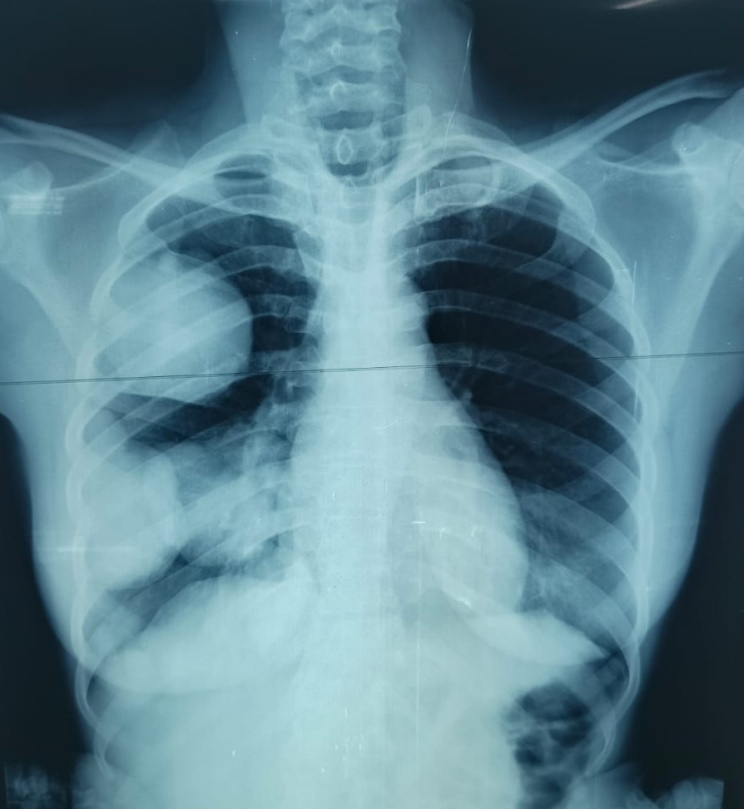

The chest X-ray revealed right pulmonary metastases, as presented in Figure 2, confirming secondary dissemination of the adenoid cystic carcinoma.

Figure 2. Chest X-ray showing right-sided pulmonary metastases, (September 20, 2025).

The chest X-ray revealed right pulmonary metastases, confirming secondary dissemination of the adenoid cystic carcinoma.